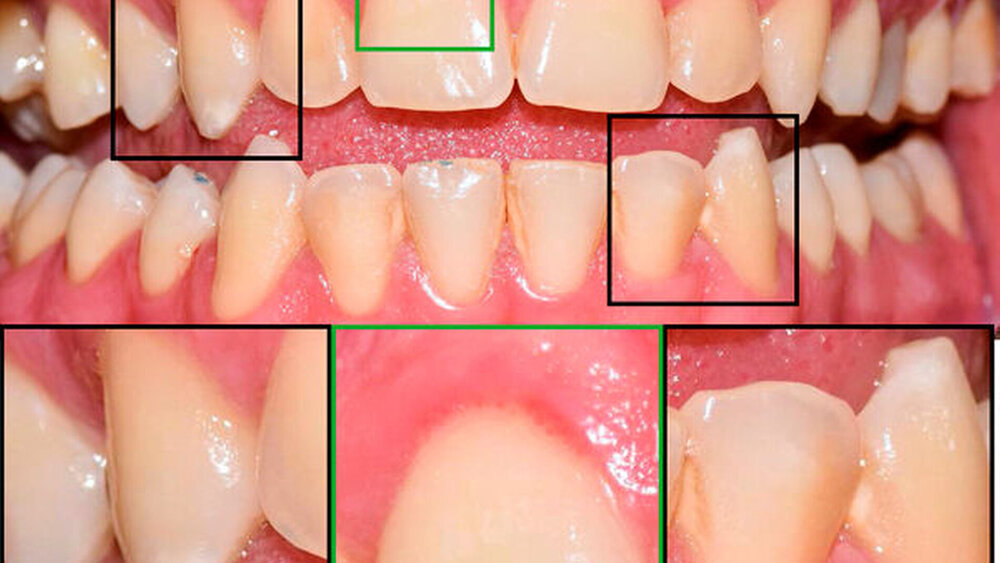

Ein 34-jähriger Patient stellte sich im August 2020 zur Wurzelkanalbehandlung an 25 und 36 und zur Versorgung kariöser Läsionen an mehreren Zähnen in der Praxis vor. Die Anamnese und der bisherige Therapieverlauf offenbarten eine hohe Kariesaktivität ab dem 25. Lebensjahr. An Molar 26 wurde klinisch und radiografisch eine profunde Karies mit deutlicher Progression mesial und distal diagnostiziert (Abbildungen 1 und 4). Gleichzeitig war der Zahn durch eine frühkindliche, metabolisch ausgelöste Hypoplasie von Schmelz und Dentin geprägt. Die Inzisivi und die unteren Molaren waren von der Anomalie nicht betroffen, stattdessen zeigten sich hypoplastische weiße Flecken an 31, 32 und 33 (Abbildung 1). Der Zahn 16 war im Alter von 21 Jahren alio loco extrahiert worden.

Nach Eröffnung der distalen Läsion an 26 wurde im vollständig kariesfreien hypoplastischen Dentin aus der präeruptiven Zahnentwicklung eine typische ausgedehnte hypermineralisierte Transparenzzone freigelegt. Die Dentinkaries wurde konventionell mit einer Unterfüllung als Pulpaschutz („Dentinersatz“) versorgt und mit Composite-Material („Schmelzersatz“) aufgebaut. Weil die Hypoplasie-Areale auch nach knapp zehn Jahren hoher Kariesaktivität nicht befallen waren, blieben diese Areale selbst an den Kavitätenrändern unversorgt (Abbildung 2).

Diese Dentin-Hypoplasie reagiert durch überlebende Odontoblasten mit einer heftigen Hypermineralisation als Dentinsklerose, die sich während der Eruption, in der eine kurzzeitige Hypersensibilität entstehen kann, weiter ausbreitet und parallel zur früheren Schmelz-Dentin-Grenze verläuft [Berten, 1895] (Abbildung 2b). Entsprechend dem Invaginationskonzept im Glockenstadium [Gängler, 1986] entstehen dann runde hypoplastische Schmelzwülste an den Rändern der Aplasie [Ida-Yonemochi et al., 2020], wie in diesem Fall bei dem Molaren. Diese bleiben ebenso kariesresistent wie das Dentin und können in jedem Lebensalter minimal-invasiv an Restaurationen erhalten bleiben (Abbildung 2c).